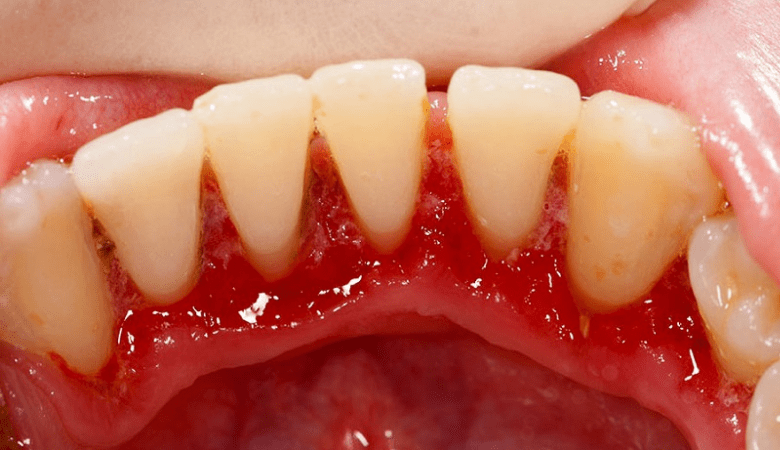

Chảy máu chân răng khi bị viêm nướu răng (nguồn: Internet)

- Chảy máu nướu: Dễ bị chảy máu khi đánh răng, dùng chỉ nha khoa, hoặc có va chạm nhẹ.